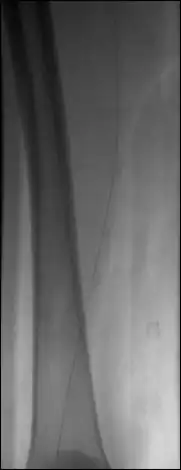

Display the image sequence in the 2D Viewer and activate the subtraction module (use Format | Customize Toolbar... if this module is not displayed in the toolbar of the 2D Viewer).

The image number used for the mask image is displayed – the first image of the sequence is the default mask. Browse through the sequence and adjust the WL/WW as needed. Click on the ‘current’ button to select another mask image.